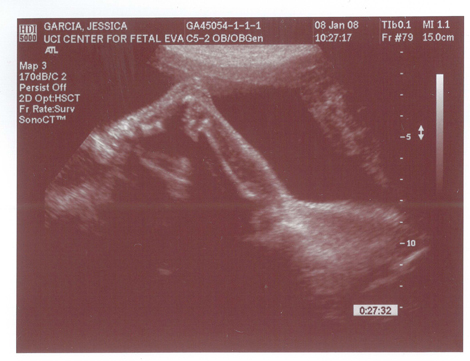

Well Im jumping on the Baby bandwagon too. Just got the first Ultrasound today about 11 weeks along.

Attached Thumbnails